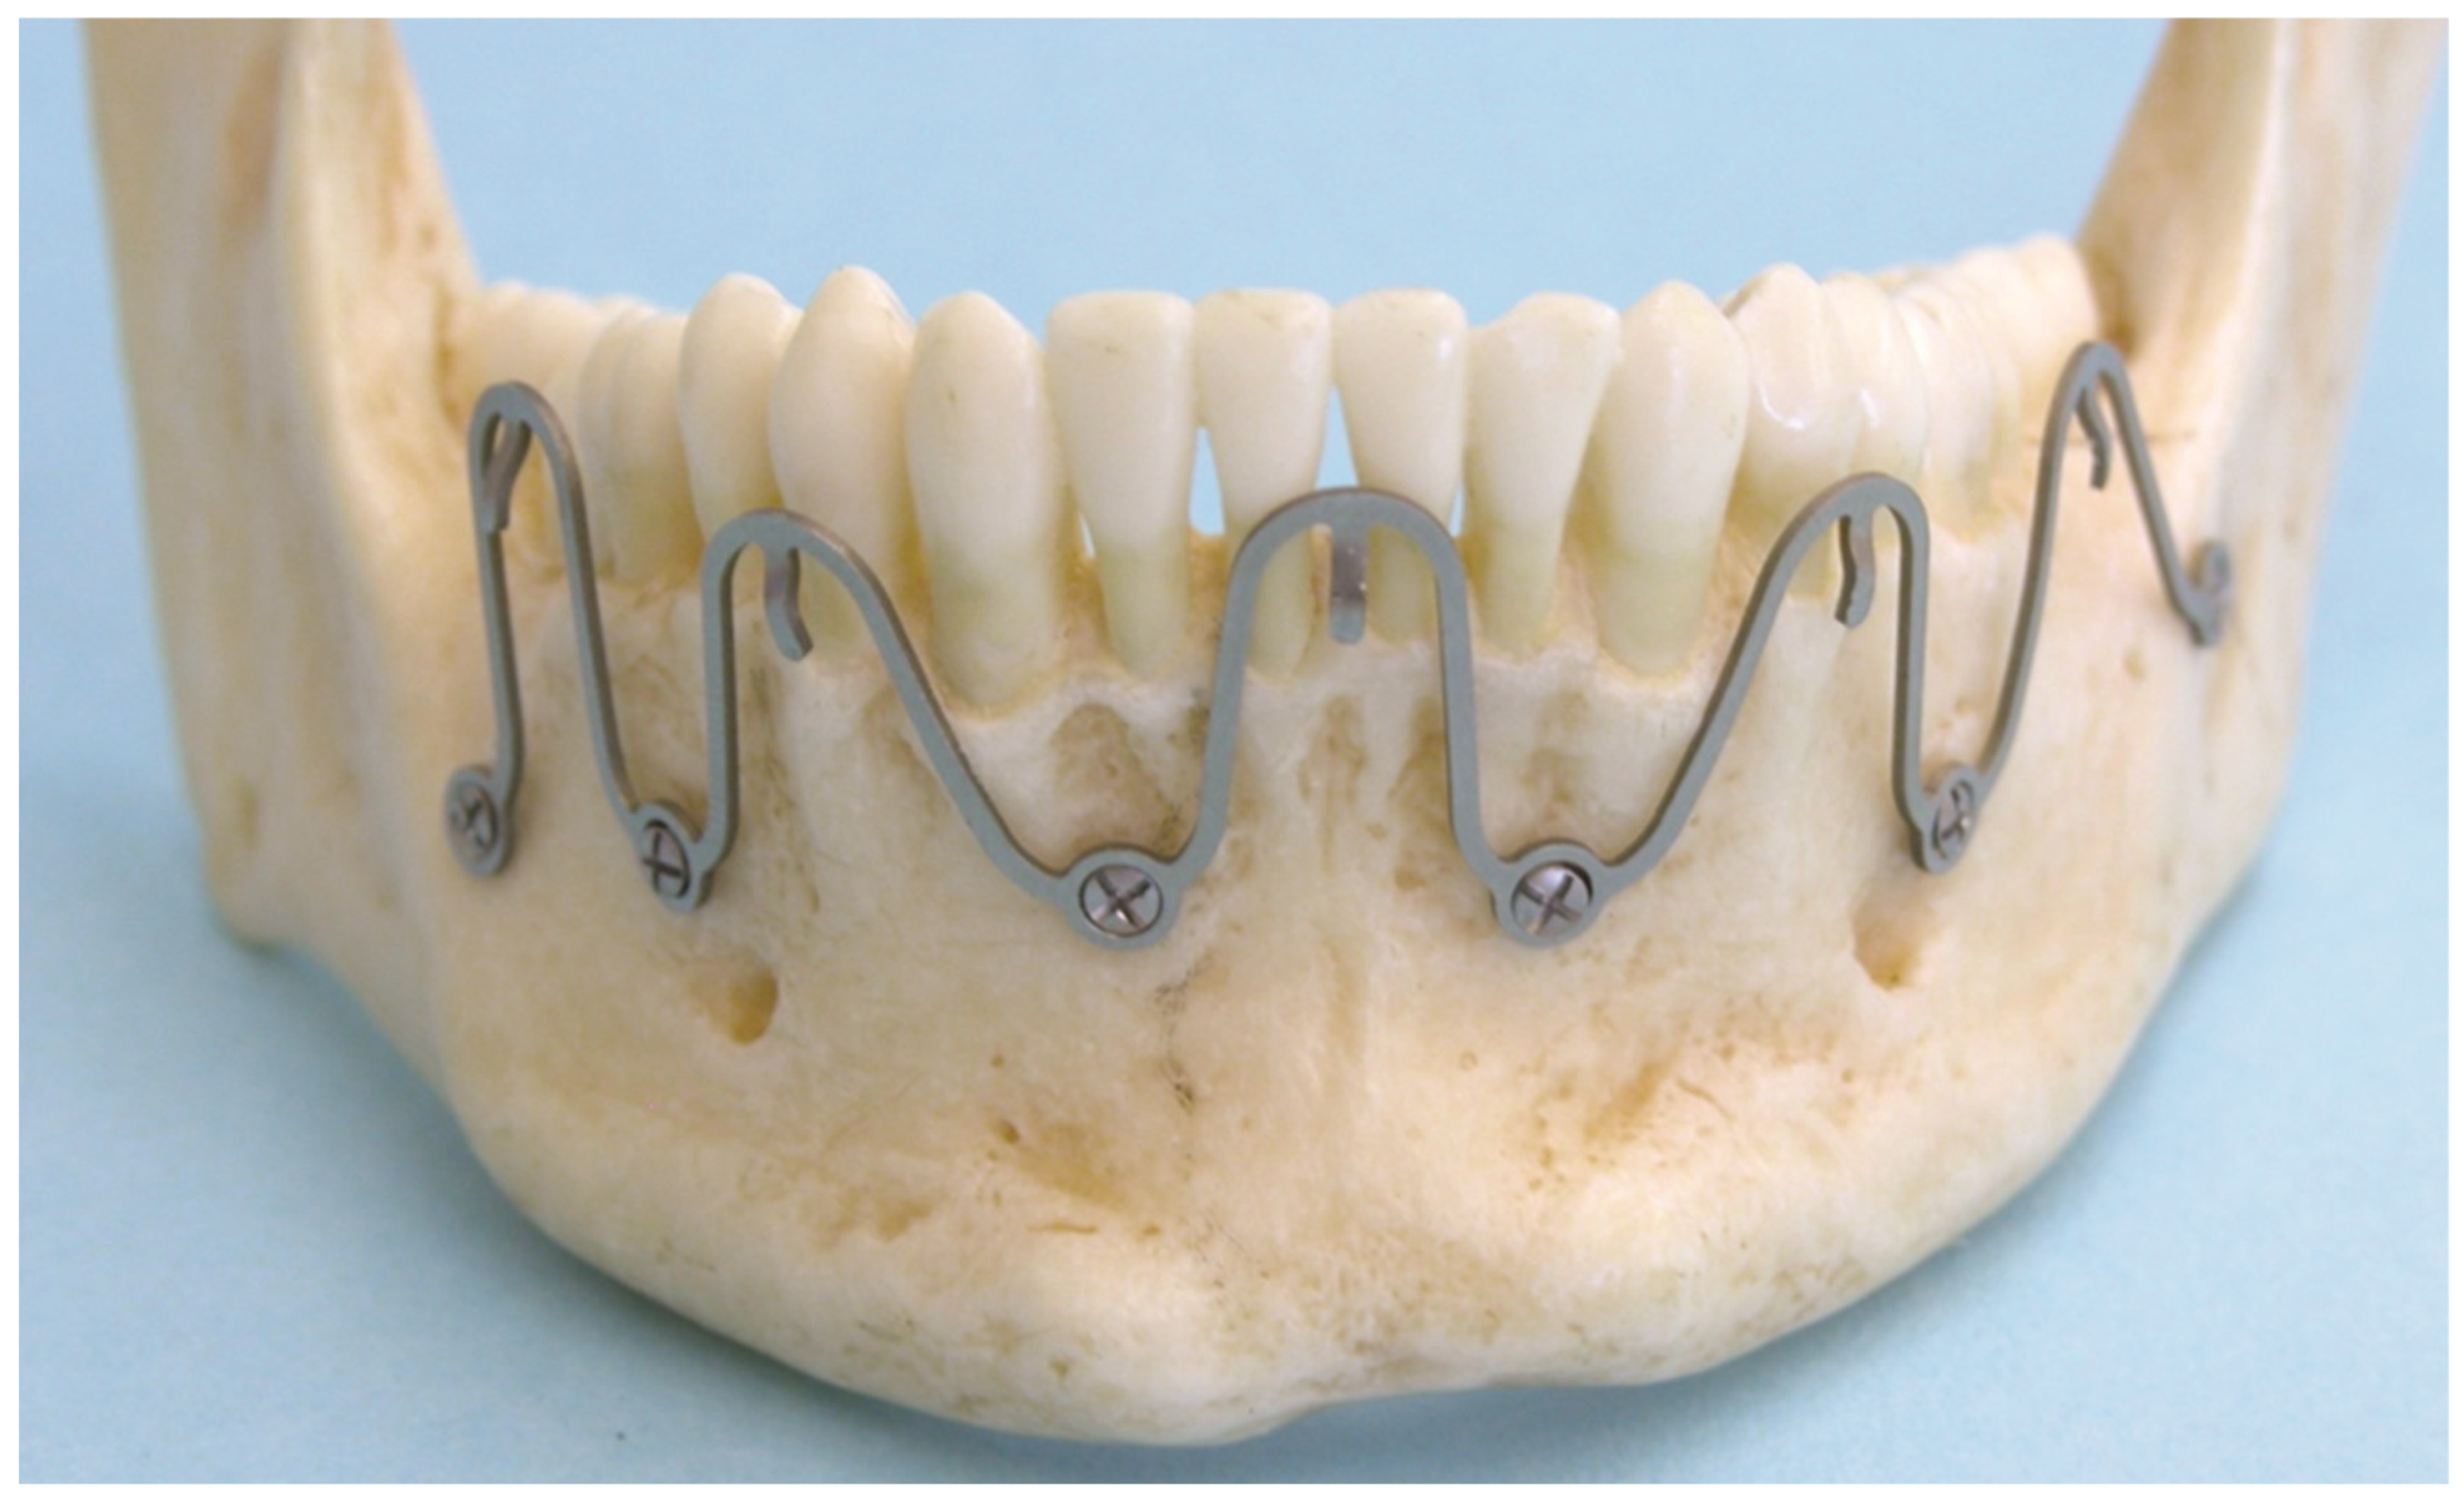

3.1. Matrix Wave Plate—Segmentation and Malleability

3.2. Matrix WaveTM Plate MMF System—Mode of Application